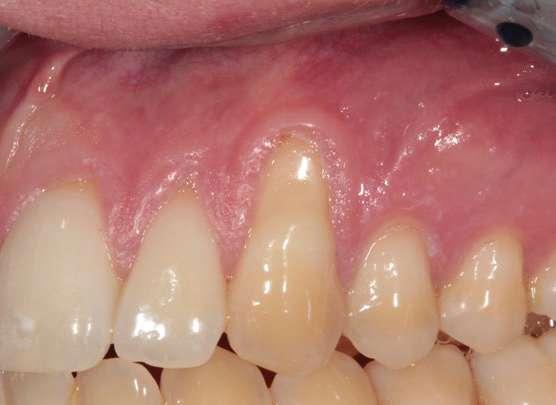

10. Seguimiento a 5 años post-operatorio. Obsérvese el buen color, textura y forma gingival, así como la estabilidad de los tejidos blandos aumentados gracias a la excelente higiene oral del paciente y el correcto mantenimiento periodontal.

Figura 8. Seguimiento a

blanqueamiento dental.

Figura

Figura 9. Seguimiento a 12 meses post-operatorio, una vez realizado el blanqueamiento dental domiciliario.

Se presentan fotografías clínicas de la evolución y seguimiento a 6 meses, 12 meses y a 5 años (Figs. 8-10). A pesar de una mínima recidiva de menos de 1 mm en la recesión del diente 2.1, es interesante y reconfortante observar la gran estabilidad clínica de los tejidos blandos, así como un color, textura y forma muy armónicos de toda la encía tratada. En gran parte también gracias a un excelente cepillado y mantenimiento periodontal.